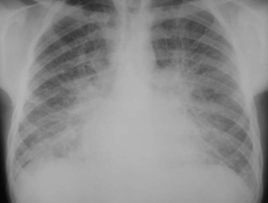

間質性肺水腫

1.肺紋理和肺門陰影邊緣模糊。

2.肺血重新分布現象,即由正常時上肺血管比下肺血管細變為上肺野血管增粗。

3.支氣管袖口征,支氣管軸位投影可見管壁環形厚度增寬,邊緣模糊,稱為袖口征。

4.間隔線陰影,其病理基礎是小葉間隔水腫。可分為KerleyA、B、C線,以B線最常見長度小於2cm,與胸膜垂直。

5.胸膜下水腫,類似胸膜增厚,不隨體位改變而變化,葉間胸膜下水腫表現為葉間裂增厚。

6.常合併心影增大,可有少量胸水。

間質性肺水腫,是肺微血管靜水壓力升高、微血管和肺泡壁通透性增加、血漿膠體滲透壓降低、肺淋巴回流障礙等原因引起的液體局限在肺泡外血管和傳導氣道周圍的疏鬆結締組織中蓄積。